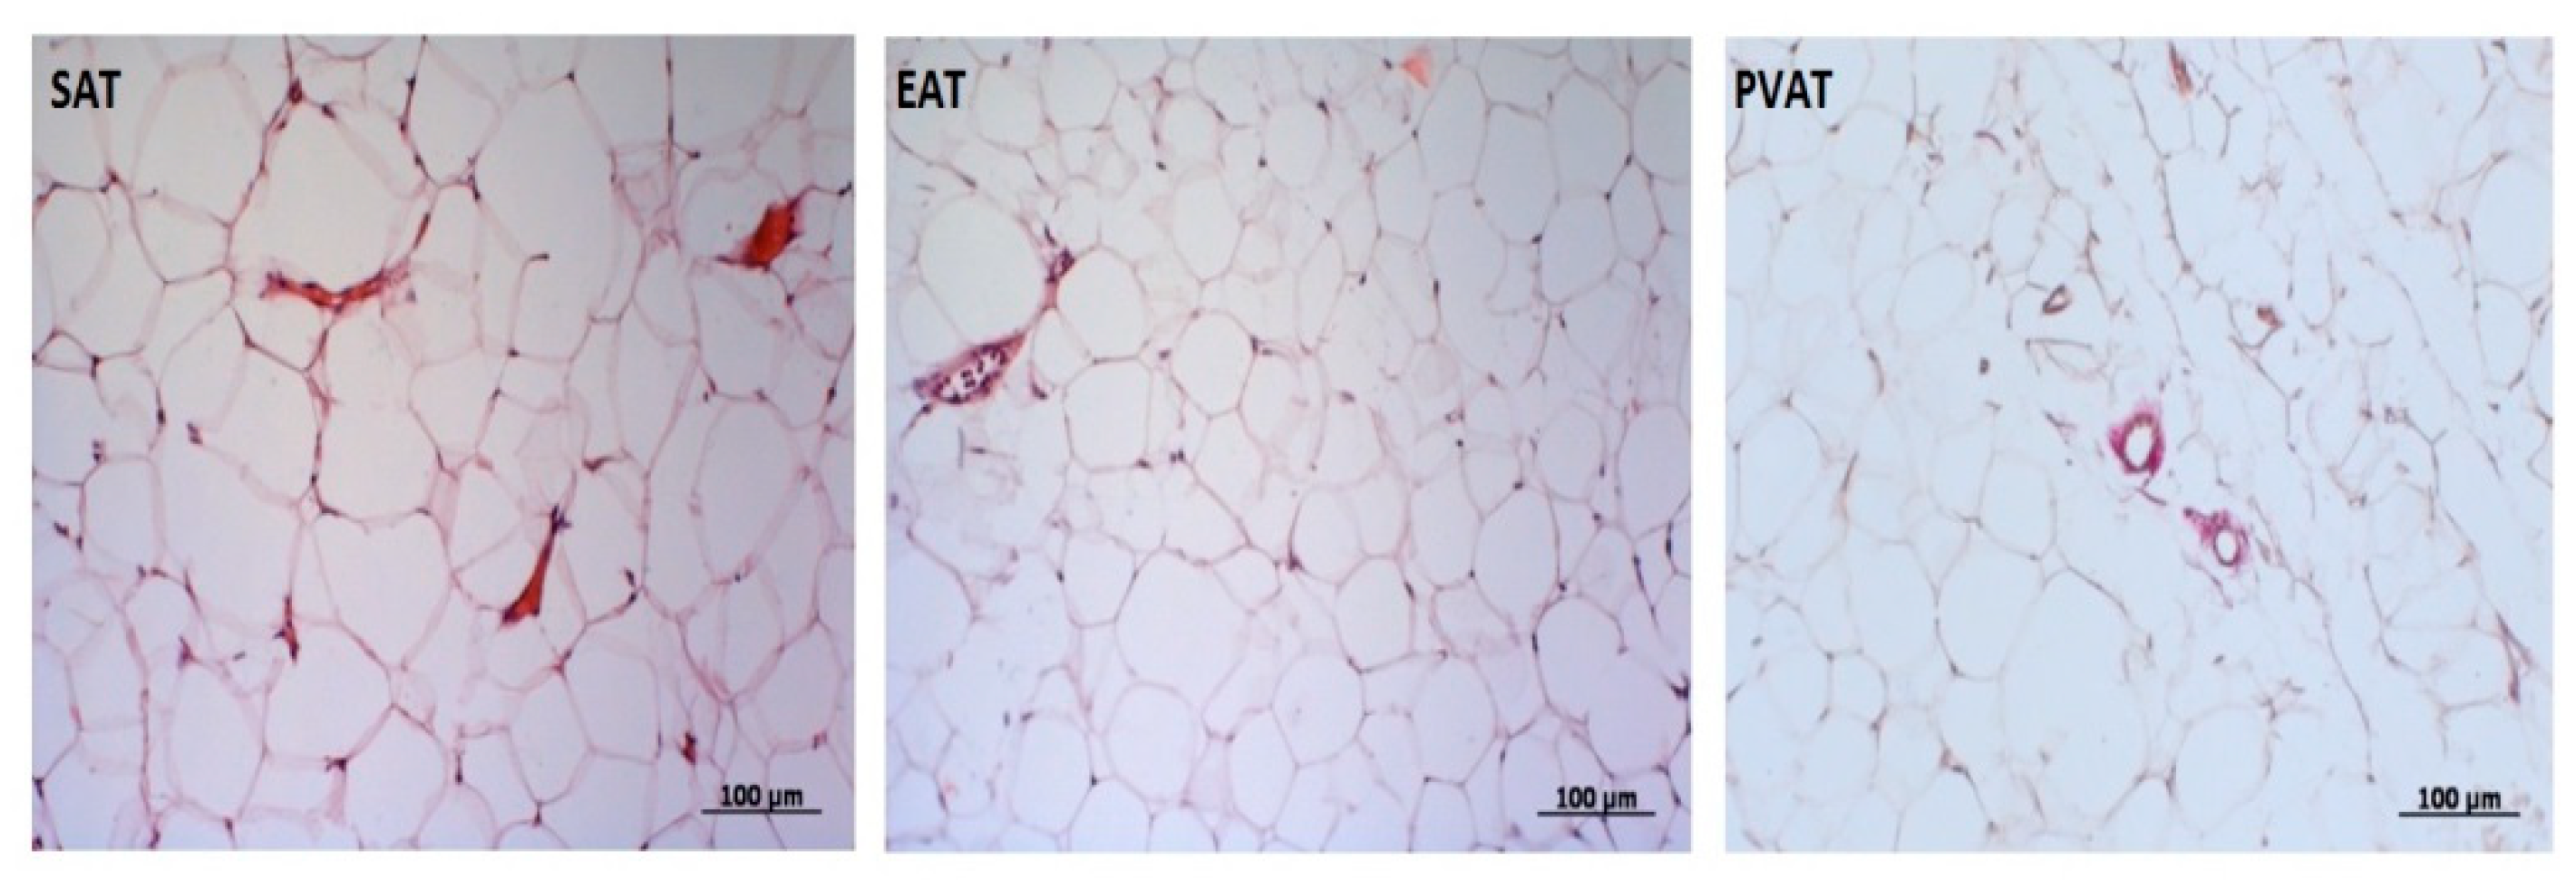

2.3. Measurement of the Area of SAT, EAT, and PVAT

3.1. Visualization of Local Fat Depots (Epicardial, Perivascular, Abdominal) in Patients with Coronary Heart Disease